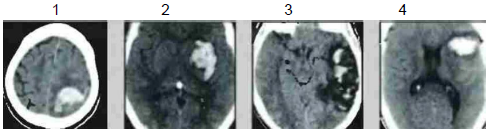

A localização das hemorragias intracranianas varia de acordo com a etiologia.

Associe as imagens 1, 2, 3 e 4 abaixo, relacionando às respectivas causas prováveis.

( ) Uso de cocaína.

( ) Infarto da veia de Labbe.

( ) Malformação arteriovenosa.

( ) Angiopatia amiloide.

A sequência correta dessa associação é: